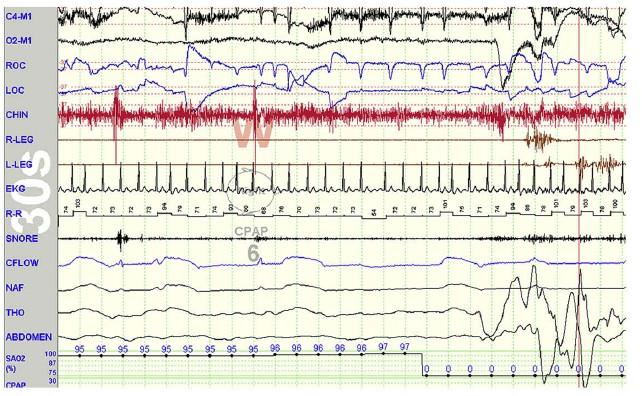

VPC, tachycardia in OSA pt

After CPAP